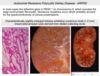

What are the 3 major pathologic features of ADPKD?

Unilateral or bilateral?

- Large, mutlicystic kidneys, bilaterally

- Liver cysts

- Berry aneurysms

What are the cysts seen in ADPKD filled with, describe its morphology

Clear serous fluid or turbid red-brown, hemorrhagic fluid

What is the gross morphology of the surface of the kidneys in ARPKD?

What does a cut section of the kidney show?

- Enlarged w/ SMOOTH surface (contast to cystic surface of ADPKD)

- Cut section shows numerous small cysts linearly arrayed in cortex ans medulla w/ spongelike appearance